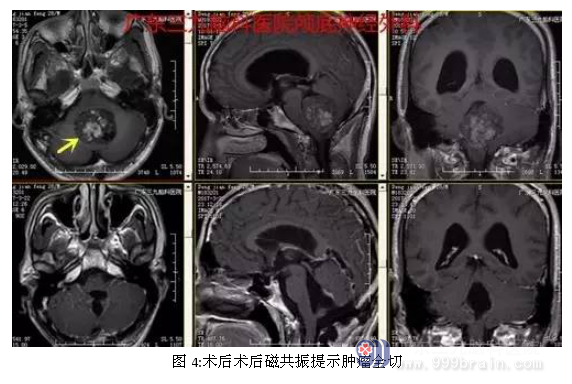

入院后完善术前相关检查,术前磁共振提示肿瘤大小约4-5cm,术前CTA提示肿瘤血供丰富,行全麻下小脑蚓部占位性病变切除术,术中肿瘤全切,术后恢复良好。术后诊断:小脑蚓部髓母细胞瘤。

手术治疗是去除肿瘤、解除颅内高压最快最彻底的方法,并为放化疗和其他治疗措施创造条件。由于肿瘤位于后颅窝,离脑干较近,因此手术全切存在一定的风险。过多的肿瘤残余将导致预后较差, 因此在不增加手术风险和并发症的前提下应尽可能多切除肿瘤。本例患者手术过程短,术后恢复快,未有明确并发症,术后复查头颅MR提示肿瘤全切。